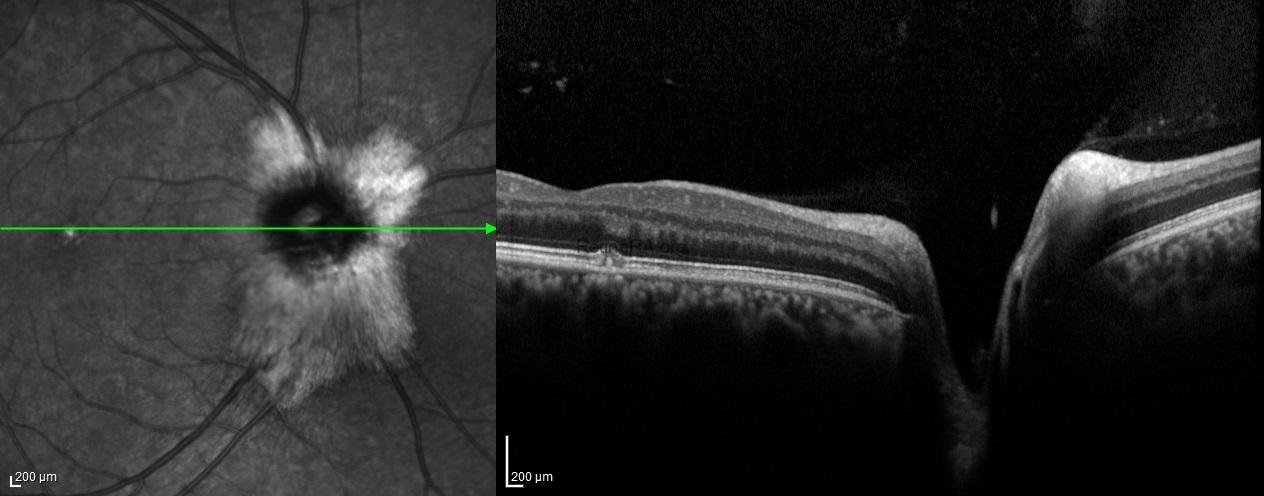

Optical coherence tomography scans through these lesions demonstrated a thickened and hyperreflective retinal nerve fiber layer.

Myelinated retinal nerve fibers are a rare, benign finding in the eye. Normally, retinal nerve fibers are unmyelinated, but in MRNF, myelin extends into the retina, appearing as white or gray striated patches near the optic disc. They are usually discovered incidentally during routine eye exams and are typically asymptomatic. While vision is often normal, MRNF can sometimes be associated with high myopia or amblyopia. Optical coherence tomography (OCT) shows a thickened, hyperreflective retinal nerve fiber layer corresponding to the lesion. No treatment is needed, but regular monitoring is recommended to rule out other retinal pathologies.